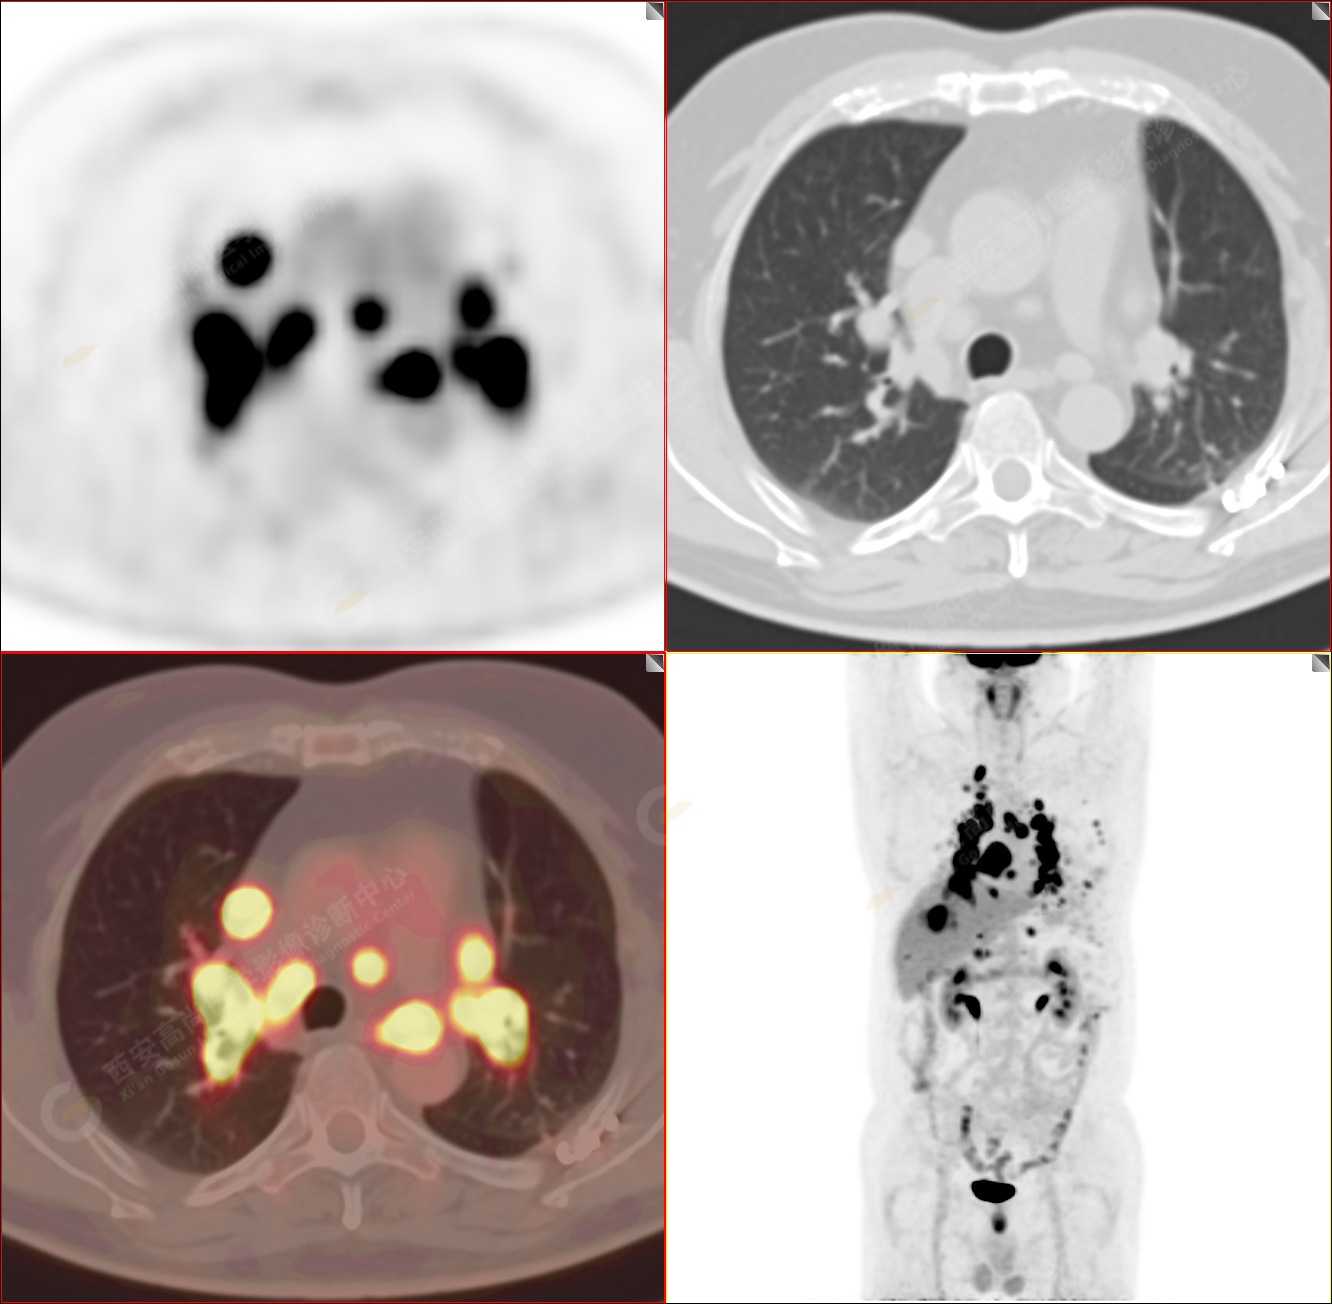

PET/CT-MR診斷結(jié)節(jié)病雙肺及全身多發(fā)淋巴結(jié)廣泛累及1例【西安高尚病例】

男性,53歲,頭暈半月入院,CT發(fā)現(xiàn)肺內(nèi)腫塊,雙肺多發(fā)大小不等實(shí)性及粟粒樣結(jié)節(jié),雙肺門(mén)及縱隔多發(fā)腫大淋巴結(jié)。病程中無(wú)發(fā)熱、胸悶氣及胸部不適。既往:左側(cè)肋骨外傷史。

PET/CT圖像